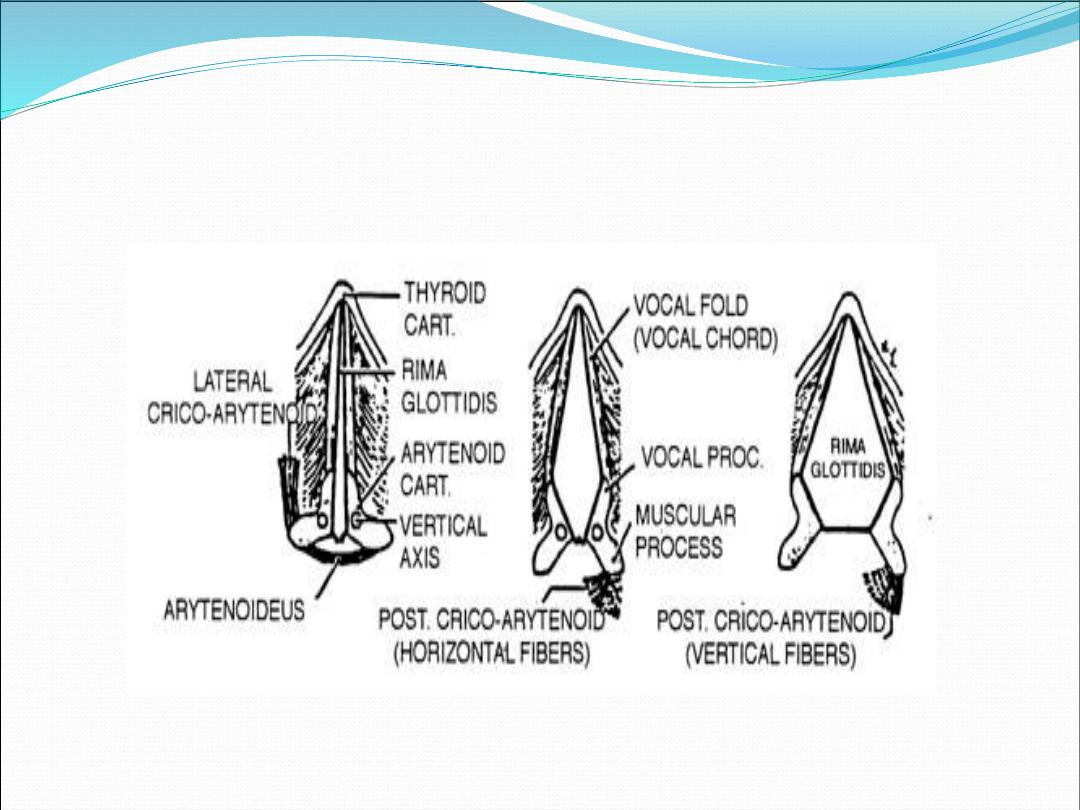

Intrinsic muscle

•

Thyroarytenoid m.

•

Interarytenoid m.

•

Posterior cricoarytenoid m.

•

Lateral cricoarytenoid m.

•

Cricothyroid m.